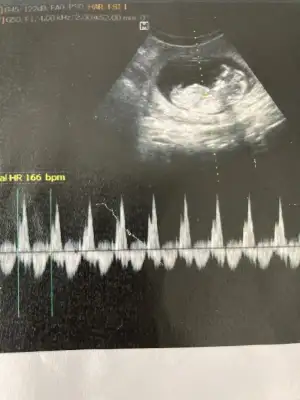

Canim yeni fotolarim geldi bakabilir misin bir Dr erkek dedi Kordon'da olabilir dedi..bugünde başka Dr gittim kıza benziyor dedi..kalp atışı olan fotoda solda bacakları nubu var yandan da baktı dr görebilmek için .sen ne düşünüyorsun 😊

Emin olmadım ama kız sanki önceki usgde kız demiştim 🙈